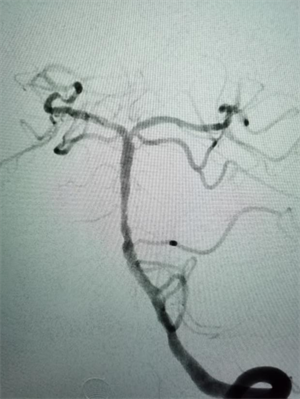

在麻醉科及脑血管介入团队的积极配合下,15:35股动脉穿刺成功,造影发现基底动脉闭塞,经导管抽吸取出血栓一枚,15:56血管再通,复查造影显示基底动脉中下段重度狭窄,后在狭窄段置入血管支架一枚。手术顺利,当晚患者神志转清醒。